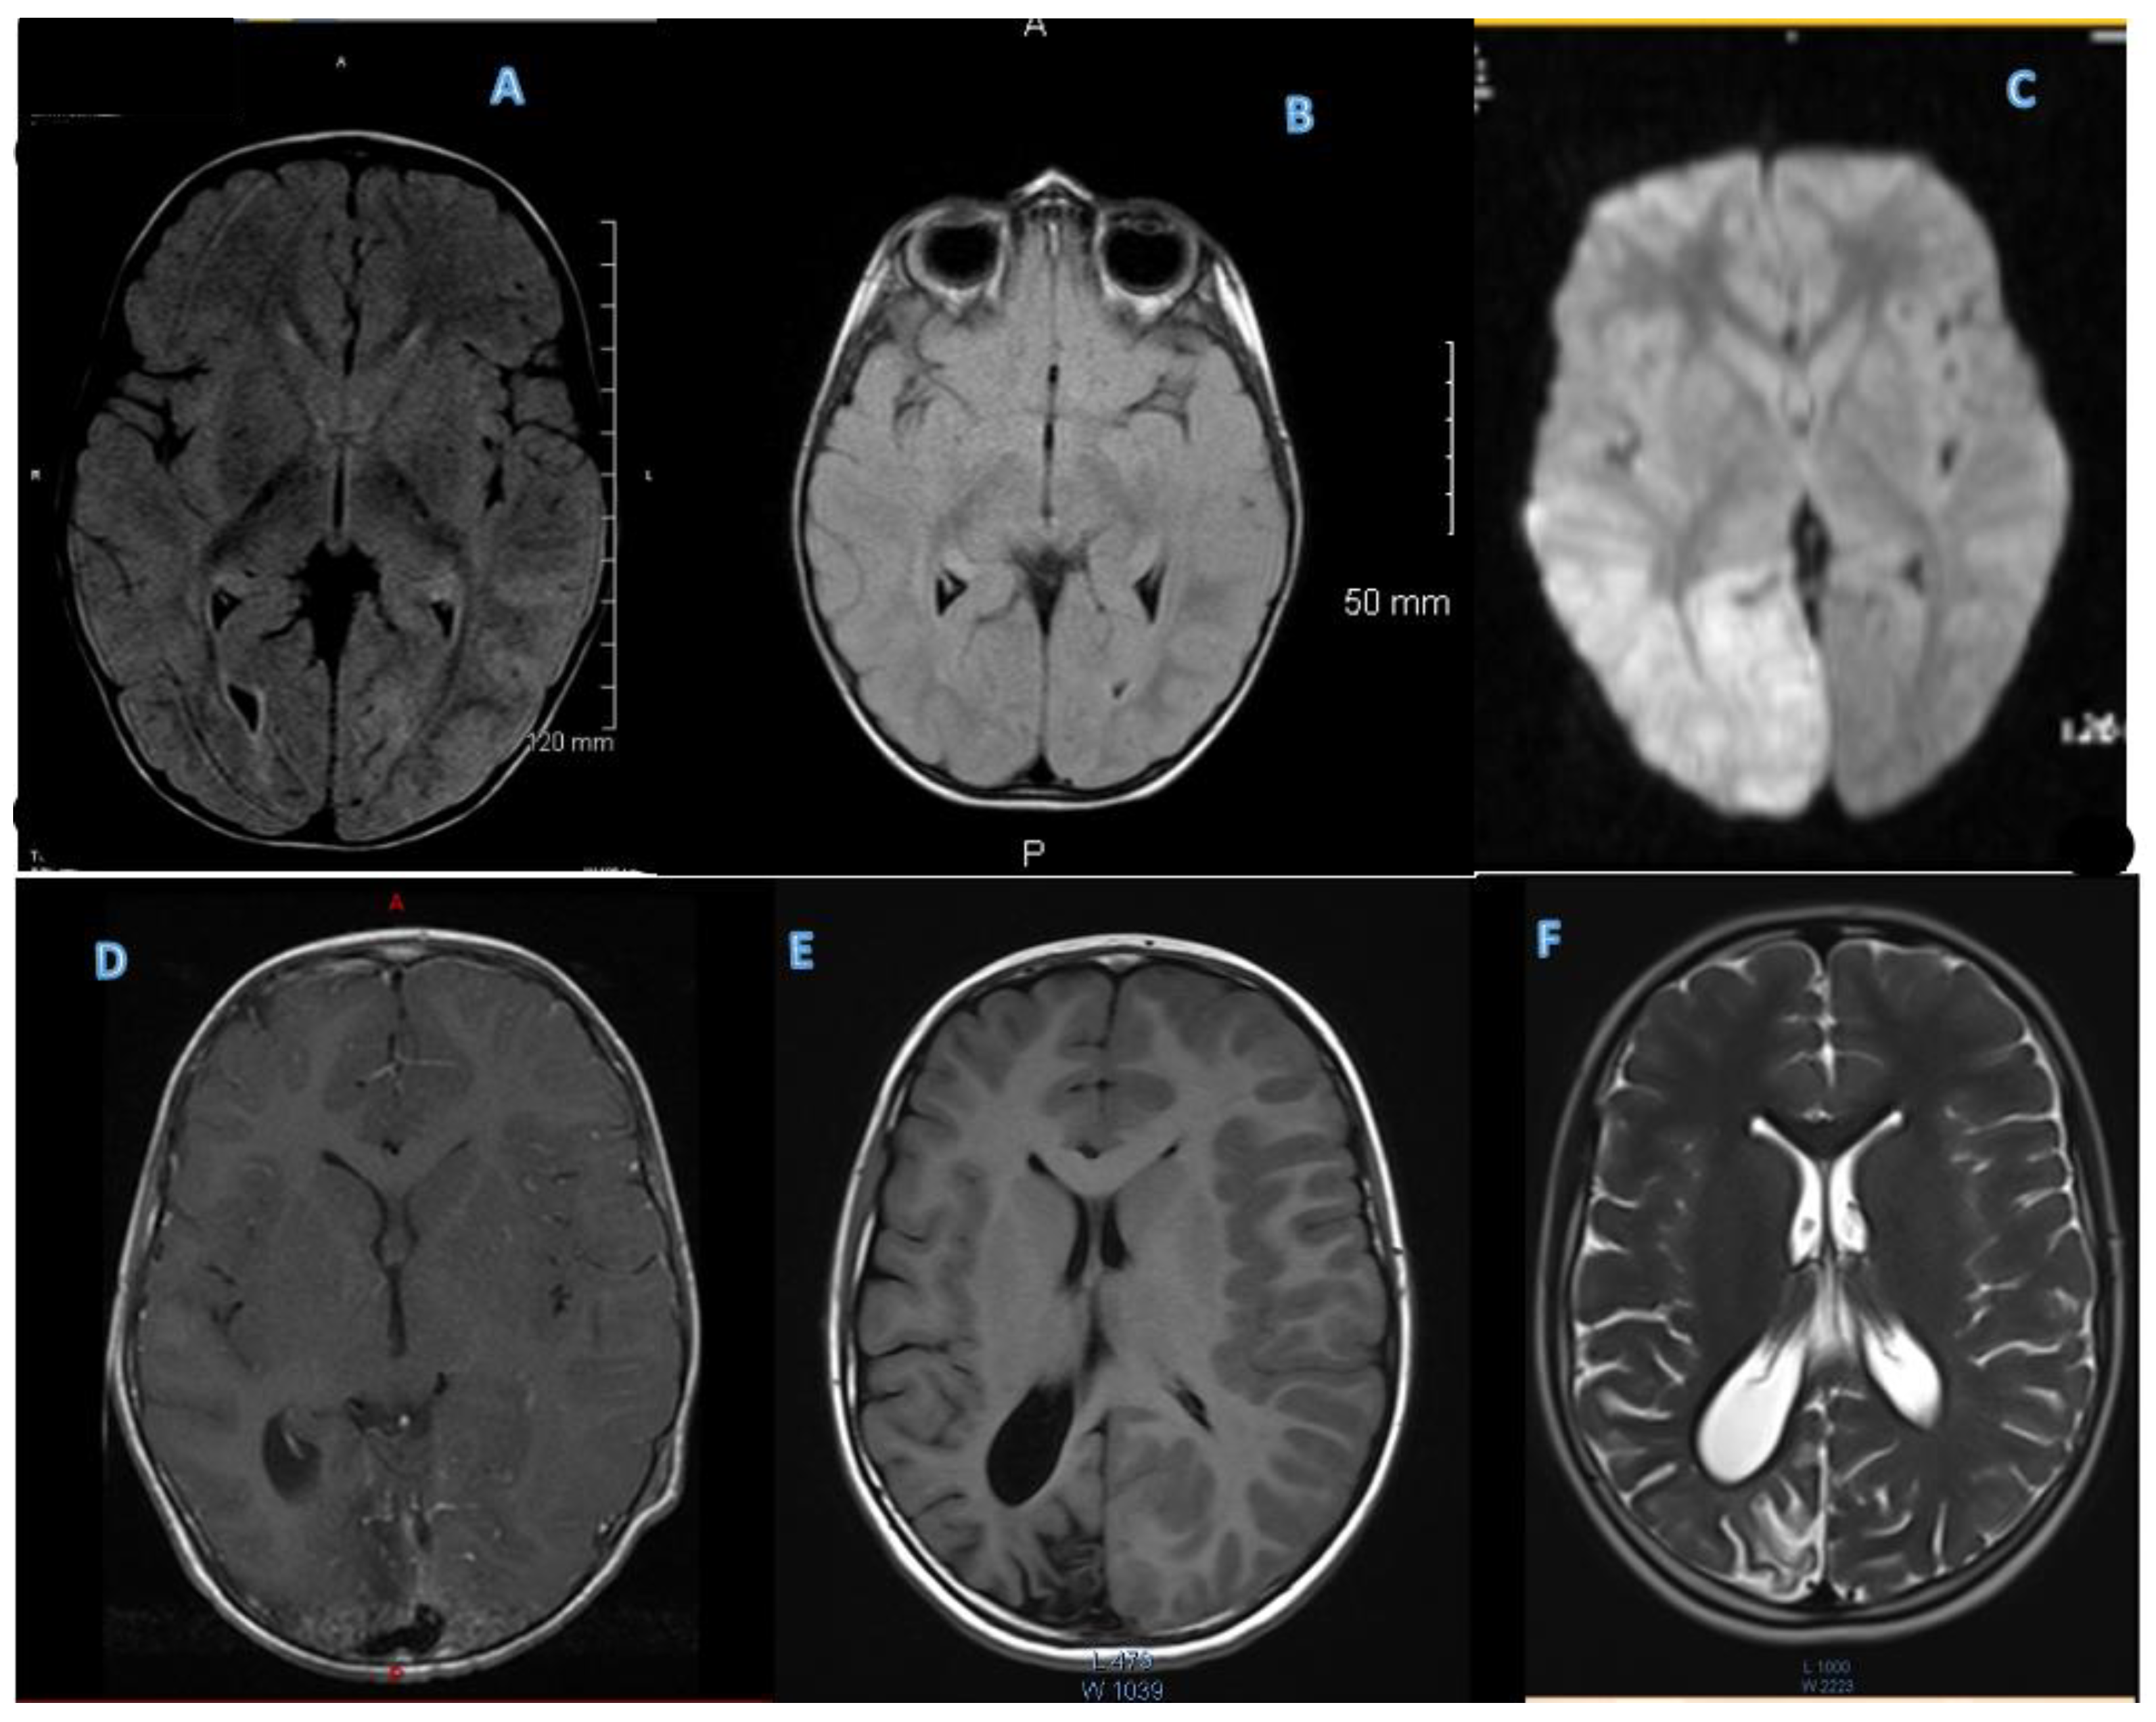

3.2.2. MRI

3.2.3. EEGs